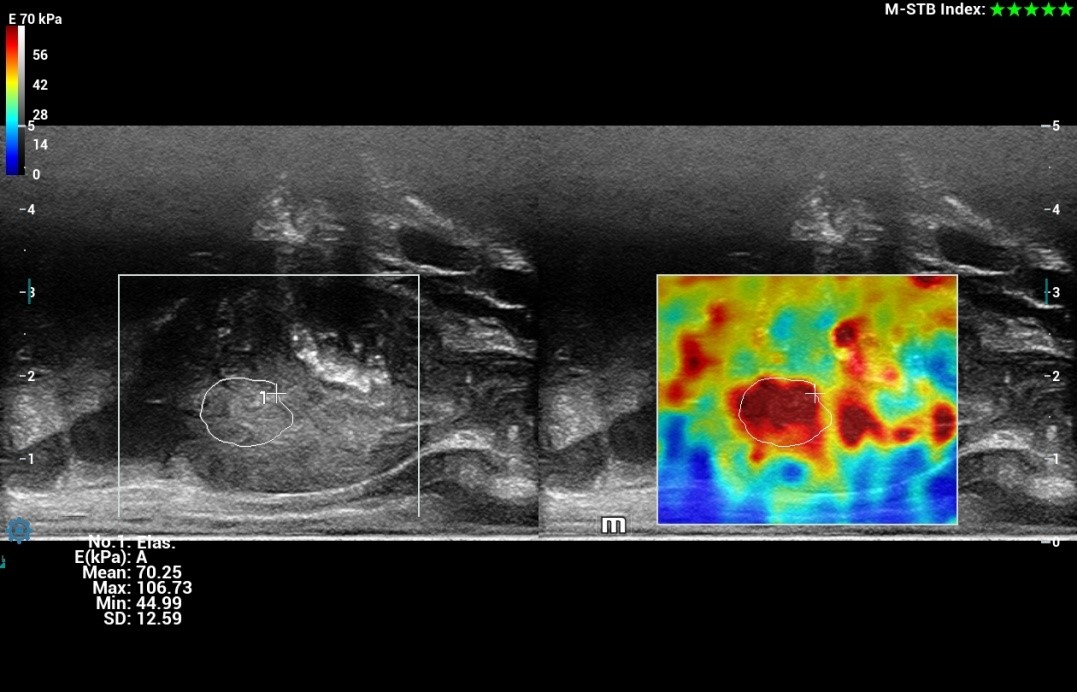

HiFR STE (Shear wave elastografia🙂 ZST+ UZV platforma umožňuje 10 krát rýchlejší STE frame rate ako u štandardných UZV prístrojov pri zachovaní hladkosti a konzistentnosti obrazu. Senzitívnejšia detekcia pohybu, lepšia stabilita vyššia presnosť. Unikátny M-STB index indikujúci pohybovú stabilitu obrazu. Presná kvantifikácia tuhosti pečene pomáhajúca pri gradingu a prognóze fibrózy a cirhózy pečene

HiFR STE Elastography: Kompletná a výkonná elastografia. Shear Wave Elastografia (HiFR STE, STQ). Strain - Natural Touch Elastografia (NTE). Vysoká citlivosť, penetrácia a presnosť. Unikátna “shell” analýza hodnotiaca infiltráciu tumoru do okolia. Automatické ohraničenie ložiska a shear wave kvantifikácia tuhosti tkaniva. Presné posúdenie tuhosti tkaniva pomôže v diagnostickom odlíšení malígneho a benígneho nálezu.

HiFR STE Elastography: Kompletná a výkonná elastografia. Shear Wave Elastografia (HiFR STE, STQ). Strain - Natural Touch Elastografia (NTE). Vysoká citlivosť, penetrácia a presnosť. Unikátna “shell” analýza hodnotiaca infiltráciu tumoru do okolia. Automatické ohraničenie ložiska a shear wave kvantifikácia tuhosti tkaniva. Presné posúdenie tuhosti tkaniva pomôže v diagnostickom odlíšení malígneho a benígneho nálezu.